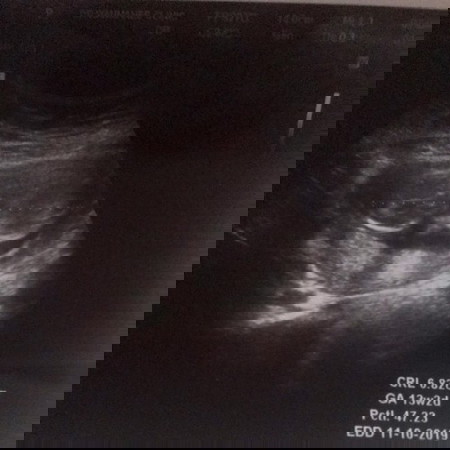

แม่บ้านไหนพอดูออกบ้างค่ะ

อยากรู้ว่าส่วนหัวอยู่ซ้ายมืหรือขวามือ ดูไม่ออกเลยค่ะ

หัวน่าจะอยู่ซ้ายน่ะคะ เห็นมีแหลมๆเหมือนจมูก

น่าจะซ้ายมือค่ะแม่ ดั้งโด่งด้วย

ทางซ้ายที่กลมๆคือหัวค่ะแม่

หัวยุซ้ายมือจ้า จมูกโด่งเชียว